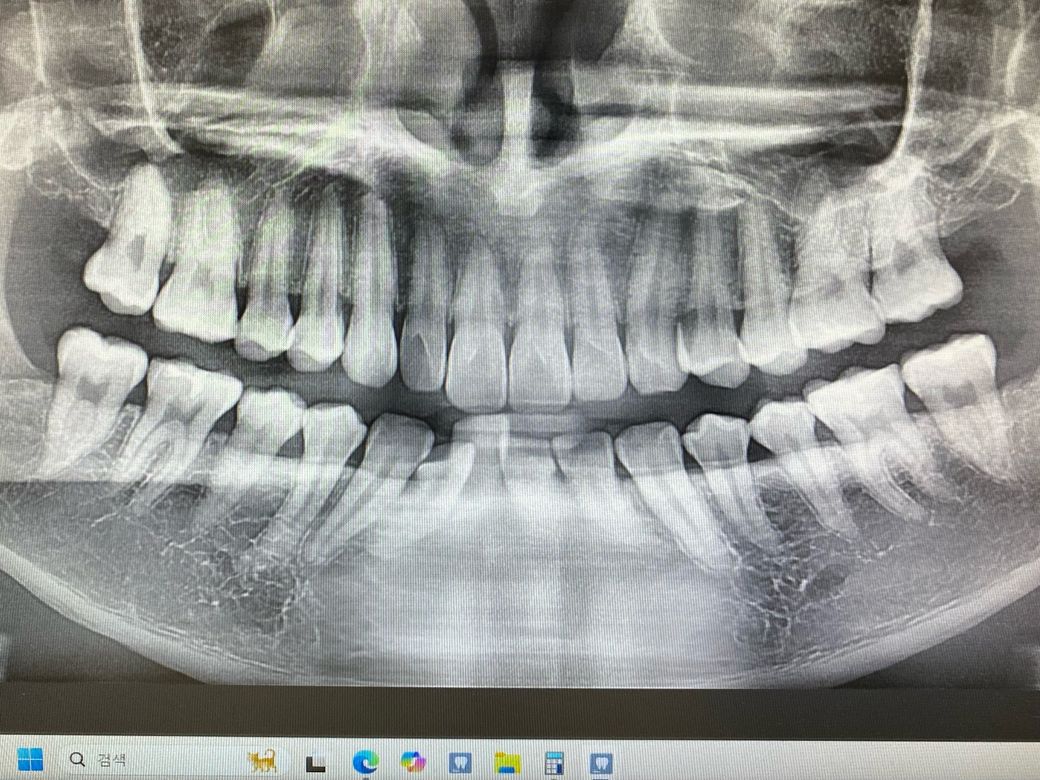

인접면 충치 지켜봐도 되겠죠? 3개의 진료

인접면 충치로 3개 치과를 갔습니다

1치과 육안으로 확인 후 근접 촬영만 하고 인레이

2치과 엑스레이 찍었지만 잘보이지 않고 있다해도

작아서 경과를 지켜보자

3치과 엑스레이 찍고 확인이 어려워 근접 엑스레이

추가 촬영 했지만 너무 작거나 안보인다

경과를 지켜보자

고민 되는건 육안으로 보인다는데 엑스레이에선

안보이거나 너무 작다는게 의아합니다

• 1번 째 사진

치아 사이에 충치가 명확히 보이는 편이며 치료를 할지 여부는 본인이 선택하시면 되겠습니다.

• 안녕하세요. 김철진 치과의사입니다.

치아 사이에 충치가 잇는건 맞으니 지금 치료를 원치 않으시면 정기적으로 검진을 받으시는게 좋을것같습니다.

• 안녕하세요. 최석민 치과의사입니다.

본인기준 오른쪽 위 작은어금니 충치 큰 엑스레이 사진상에서 보이네요 치료해야할 정도입니다